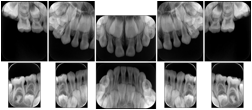

2. A patient requests cosmetic surgery to enhance their facial appearance. The case requires consultation between an orthodontist in New York and an oral surgeon in California. The cephalometric series of 2D projections constructed from a volumetric CT data set that is used for the discussion is arranged by a Structured Display for transfer between the two practitioners.

Cephalometric Series Structured Display

Figure OO-2. Cephalometric Series Structured Display